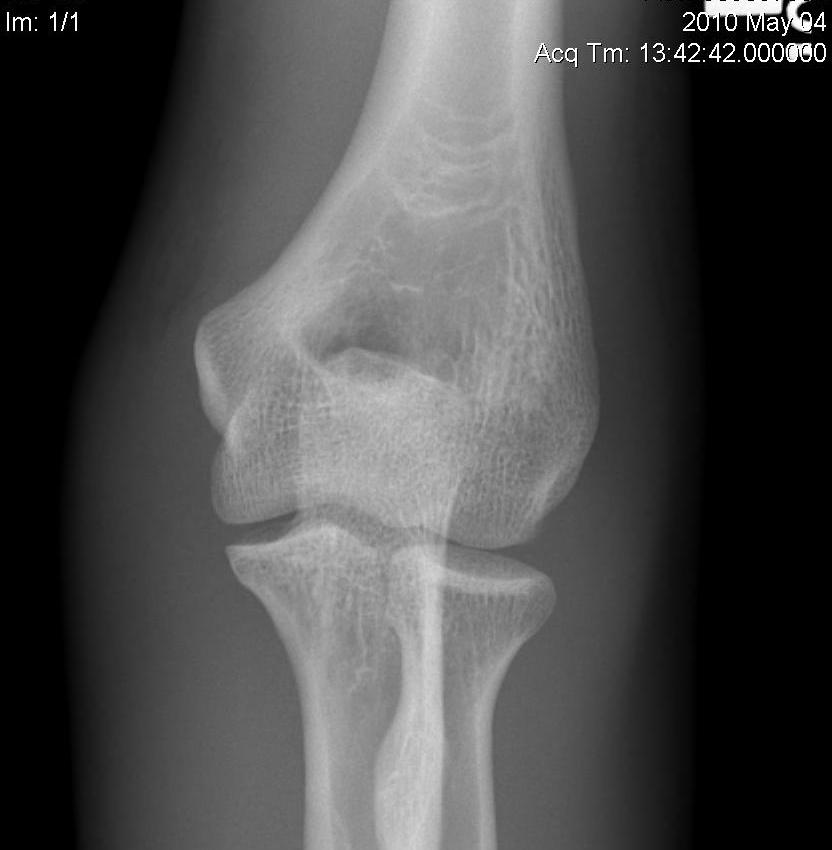

OTA / AO Classification

Type A: Extra-articular fracture

Type B: Partial articular fractures

Lateral condyle Medial condyle

Type C: Complete articular fractures